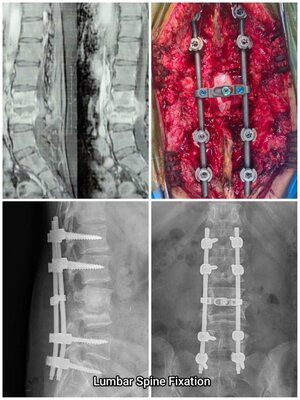

Lumbar Spine Surgery with Implant Fixation | Dr. Rahul Sharma

The spine is a vital part of our body's structure, supporting our posture and enabling a range of movements. However, it’s also susceptible to v...

Read More about Lumbar Spine Surgery with Implant Fixation | Dr. Rahul Sharma